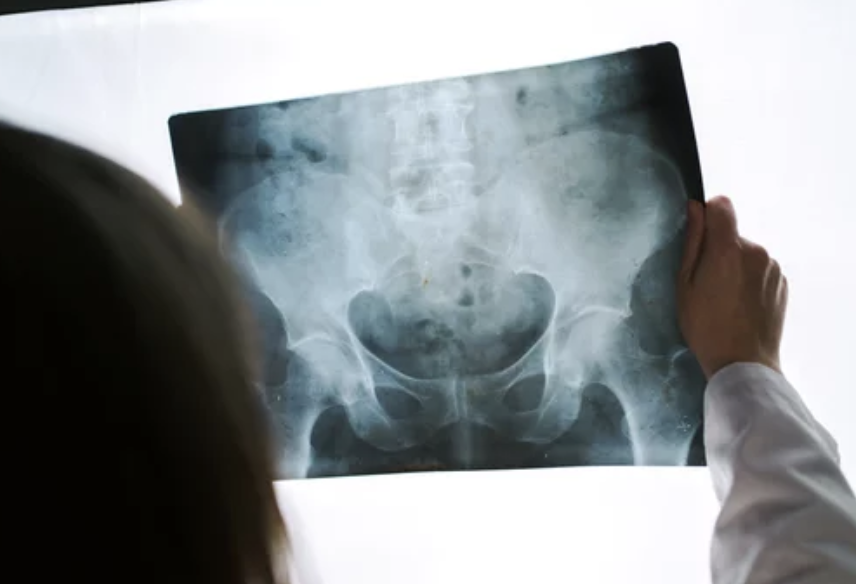

고관절 통증의 진단과 치료는 의사의 전문적인 평가와 조언이 필요합니다. 의사는 환자의 증상을 평가하고 필요에 따라 신체 검사나 영상 검사를 통해 진단을 내릴 수 있습니다. 관절염 등의 염증성 질환인 경우 항염증 약물이나 생활습관의 변화를 통한 관리가 필요합니다. 골관절탈구나 심한 손상의 경우 수술이 필요할 수 있습니다. 물리치료나 침술 등의 보조 요법도 통증을 완화하는 데 도움이 될 수 있습니다.